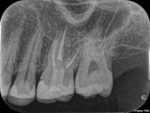

1980年代半ばに、歯冠修復の失敗によって根管充填された根管内に細菌感染が起こることが注目されるようになりました。1995年、RayとTropeによって歯内療法の質と歯冠修復の質が予後に及ぼす影響について大規模な調査が行われました。テンプル大学で治療を行った1010本の根管治療歯のX線写真を調査し、歯内療法の質と歯冠修復の質、根尖部の状態を評価しました。尚、ポストのある歯は除外されました。評価基準は以下のとおりです。

・良い歯冠修復(=Good Restoration):被せ物がピッタリ合っている。

・悪い歯冠修復(=Poor Restoration):被せ物のヘリが合っていない、隙間や段差あり。二次う蝕。